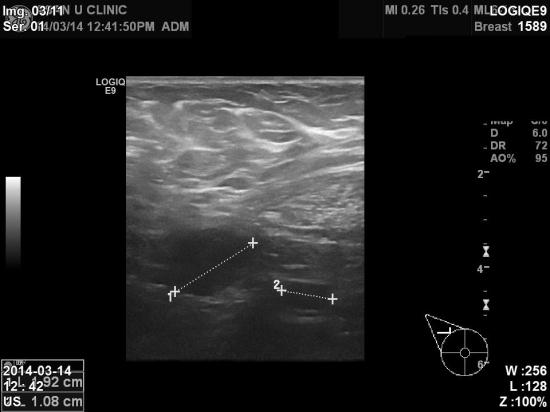

우측겨드랑이에도 림프절 비대소견있어

조직검사 및 림프절 세포검사결과 침윤성 유관암 및

겨드랑이 림프절 전이로 진단되었습니다.